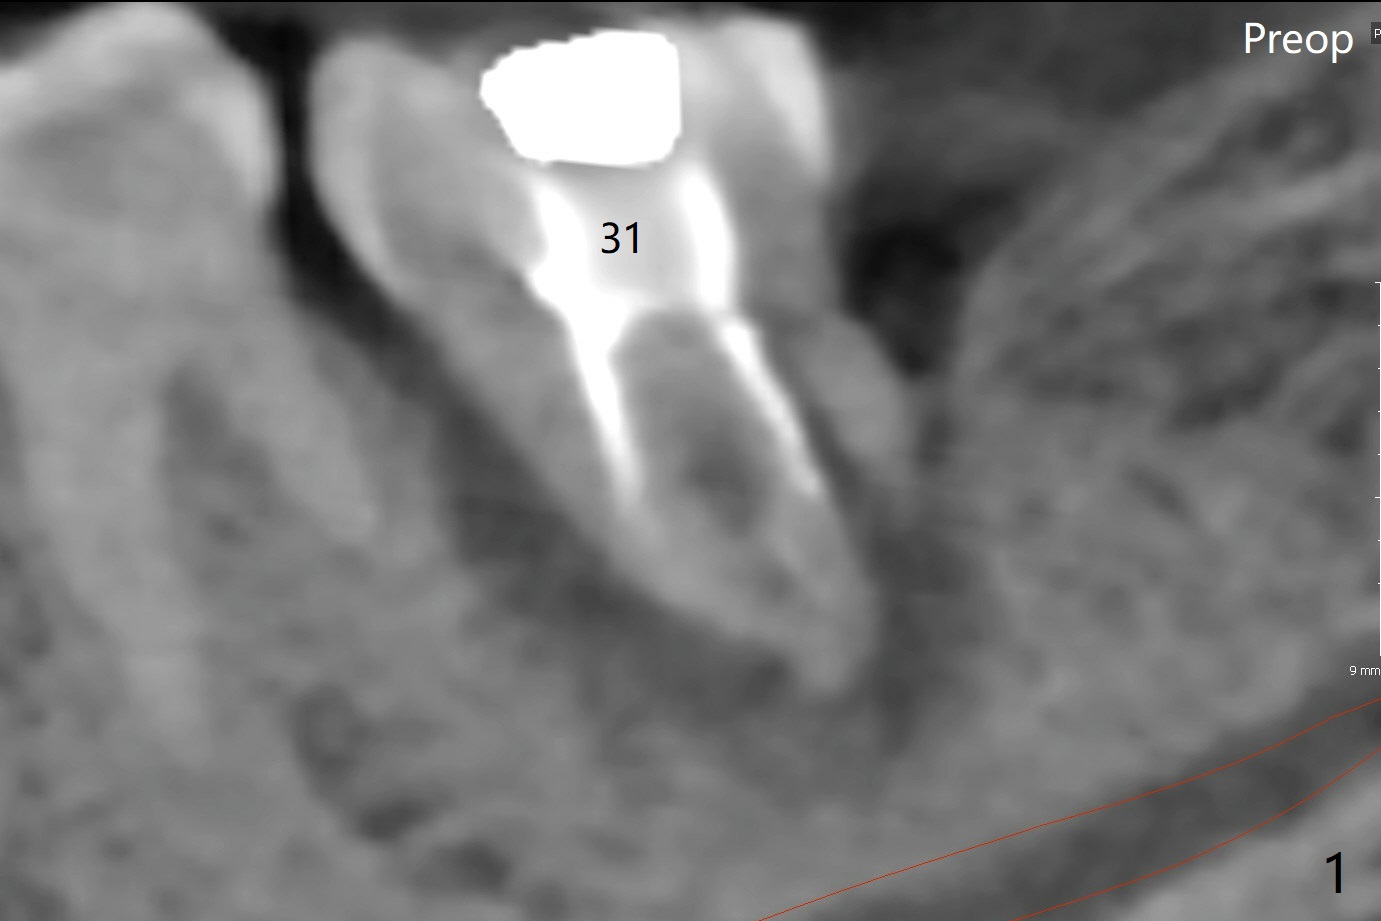

CBCT shows thin cortical bone formation mesiodistally 6.5 months post socket preservation with allograft with PRF at #31 (Fig.3 ^, as compared to Fig.1). The socket appears to be closing buccolingually 10 months postop (Fig.6 arrowheads, as compared to Fig.4). Bone density increases from 1100 units to 1,200-1,400 units 6.5 to 10 months. With underprep (4 mm), a 5x10 mm implant is placed with ~ 50 Ncm with guide (Fig.7). Following a 5.5 mm profile drill, a 5.5x3 mm healing abutment is placed (Fig.8); the implant plateau appears to be supported by the graft bone (*). The implant remains subcrestal 4 months postop (Fig.9).